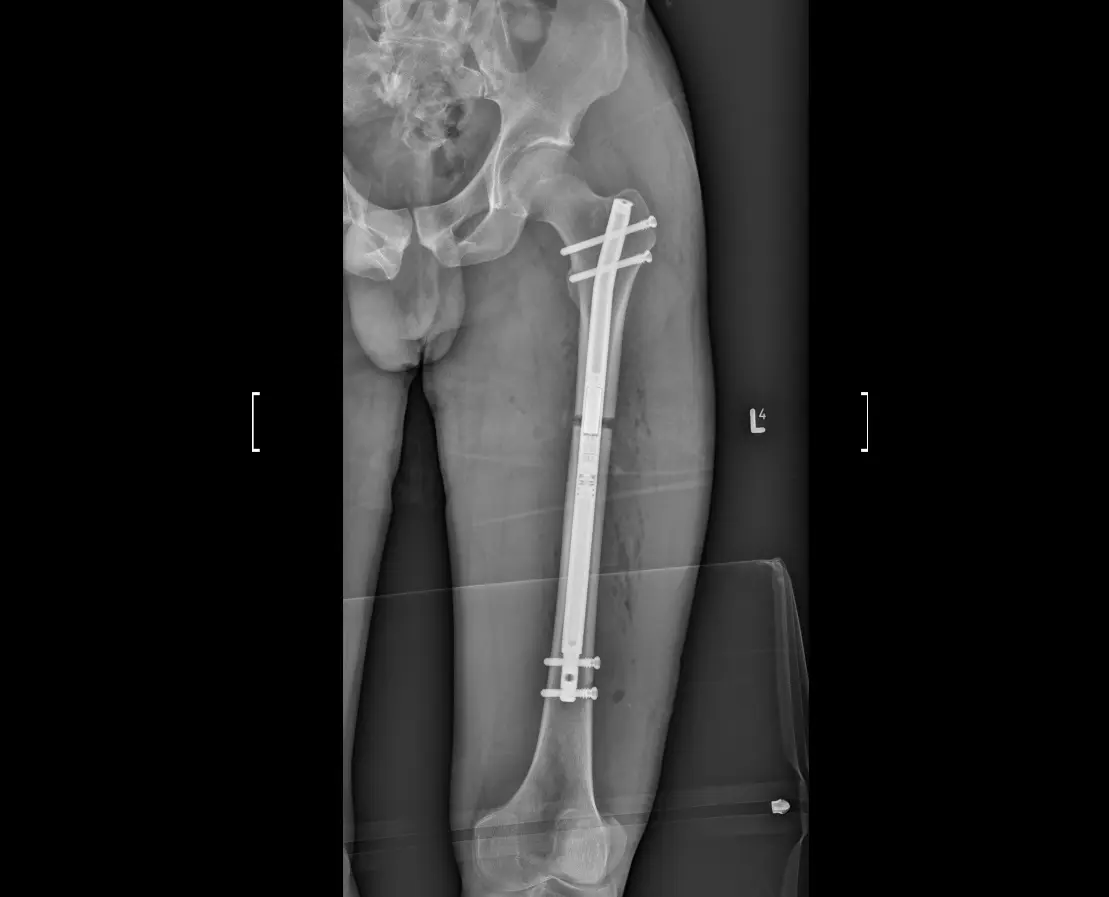

X-ray of the femur of a patient after limb lengthening surgery.